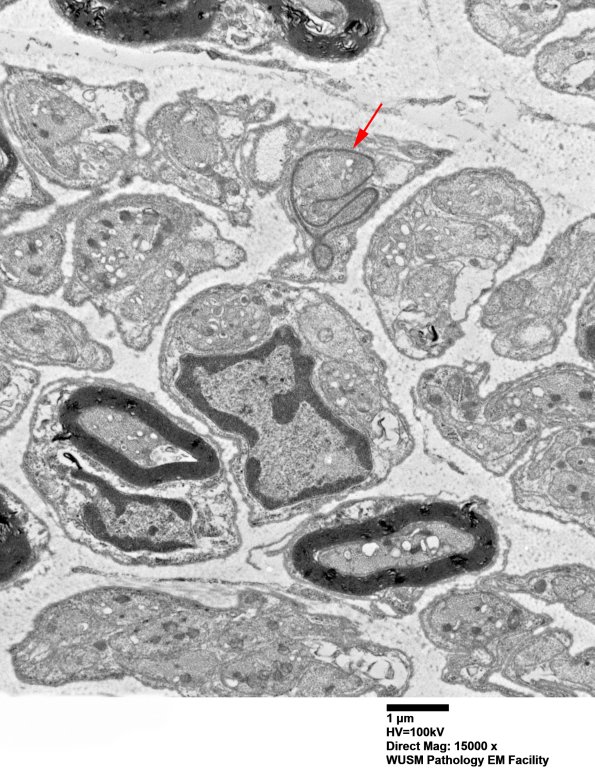

There are numerous axons which will become unmyelinated Remak bundles as well as increased numbers of small thinly myelinated axons (arrow). (electron micrograph)